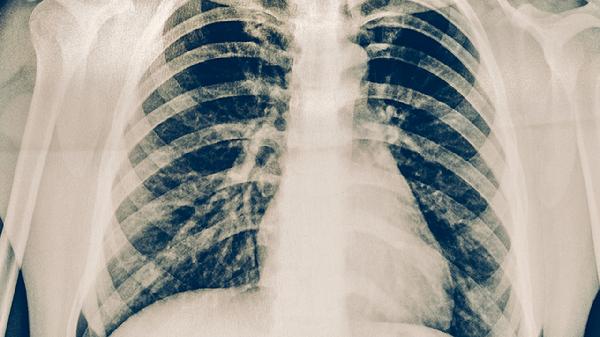

肺癌这个"沉默杀手"正悄悄逼近越来越多的人。最近体检中心的数据显示,肺部结节检出率比五年前翻了一番。别以为只有老烟枪才会中招,那些看似无害的生活习惯,可能正在摧毁你的肺功能。